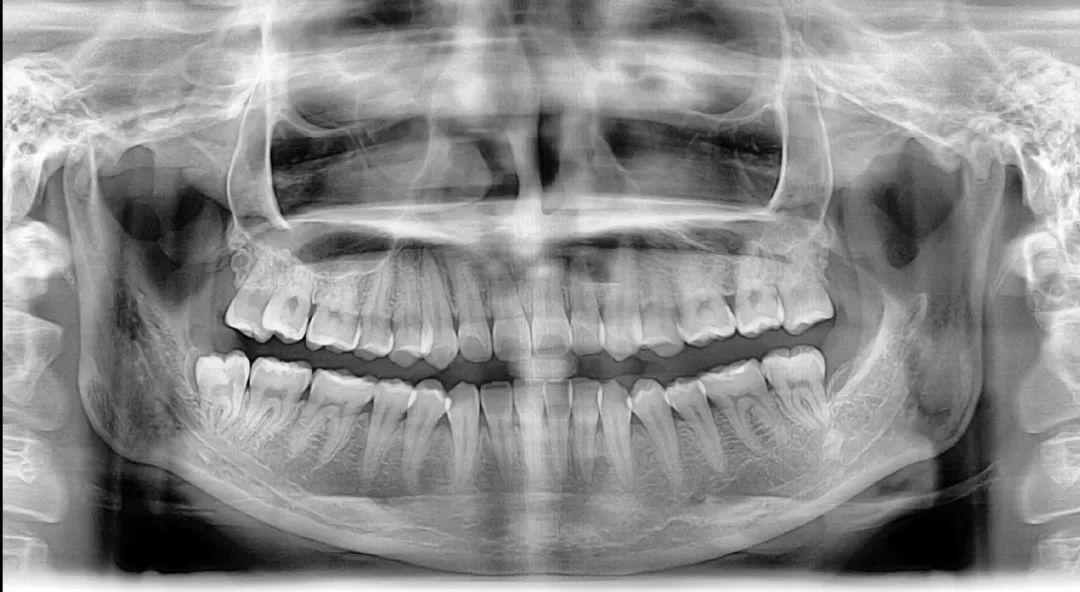

矫正前,拍摄牙齿全景片和头颅侧位X光片是必不可少的一步 | www.lovelytooth.com

那么一个正规的牙齿矫正程序应该是什么样子的呢?以我自己为例,当年为了体验一把隐形牙套这个新科技,我找到了早在国内研究隐形矫正的师姐。真正资质合格的隐形正畸操作繁琐复杂,医生首先检查了我的牙齿情况,并且发现了我早已存在,但隐匿的蛀牙,然后从前后左右上下各个角度拍摄了大约数十张牙齿以及面部的照片,详细记录了笑起来露出牙齿的程度、牙齿向外倾斜的程度、牙齿中缝是不是正好对齐、有没有脸部不对称的情况。

接下来,我拍摄了曲面断层和投影侧位片以及全口牙齿锥形束CT,用于描绘标志点进行线角的测量,后用3D扫描仪记录了牙齿的全貌,牙齿矫正的设计不仅包括表面上的牙齿排列、侧面像的协调,而且还要深入到骨骼结构、发育潜能、动静态的颌位关系。